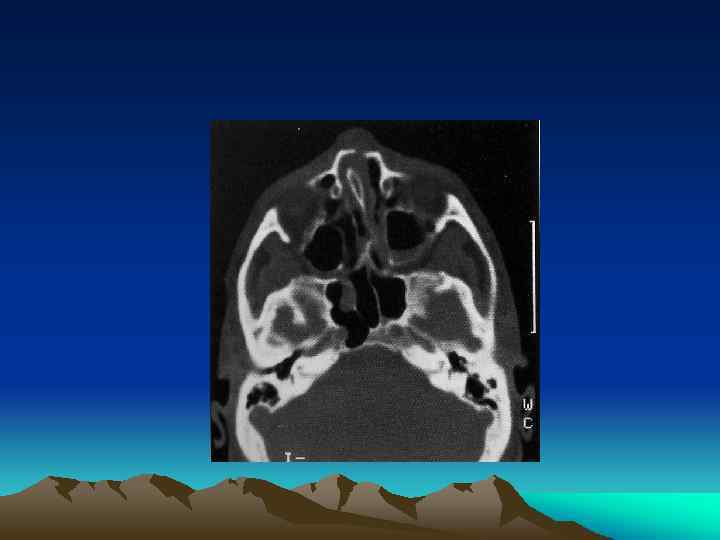

Facial Plain Films Ø Largely been replaced by computer tomography (except for the mandible) Plain Film Mandible Series and Panorex Computed Tomography (CT) Ø Most informative radiographic exam fro head and neck Trauma Ø Axial and coronal facial CT with bone and soft tissue window, 2 -3 mm sections

INTRODUCTION Ø Ø Ø Orbital Bones Optic Canal& Orbital Fissures Contents Sign& Symptoms

TYPES Ø Pure Ø Impure

Management Ø Indication for Surgical Intervention Ø Contraindications for Surgical Intervention: hyphema, retinal tear, globe perforation, only seeing eye sinusitis, frozen globe Ø Ophthalmological Evaluation Ø Timing : 1 week Ø Technique